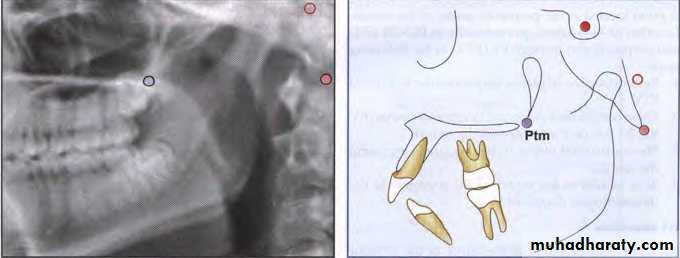

Pterygomaxillary Fissure (Ptm)

A bilateral teardrop-shaped area of radiolucency, theanterior shadow of which is the posterior surfaces of

the tuberosities of the maxilla.